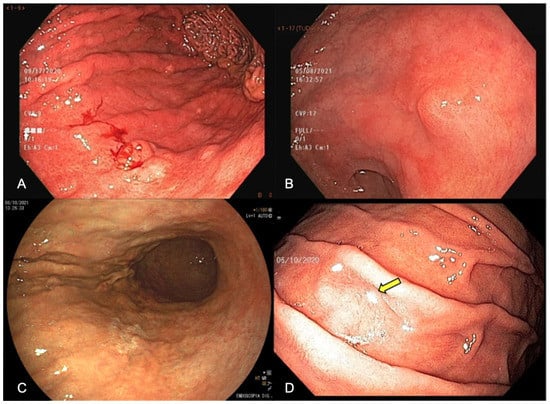

Abstract

3. White-Light Endoscopy (WLE)

3.5. Obtain Index Images

3.6. Target Biopsies of Suspicious Lesions